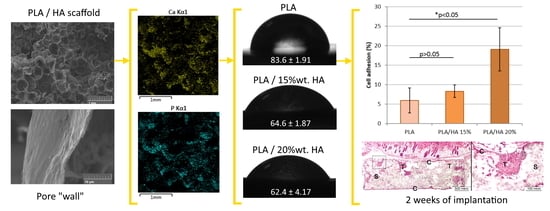

3.1. Microstructure Analysis

3.3. Sample Composition Analysis

3.6. Assessment of Surface Hydrophilicity

3.7.1. Cell Adhesion

3.8. In Vivo Implantation and Histologic Analysis

| Sample | The Value of the Wetting Angle, ° |

|---|---|

| PLA | 83.6 ± 1.91 |

| PLA/HA 15% | 64.6 ± 1.87 |

| PLA/HA 20% | 62.4 ± 4.17 |